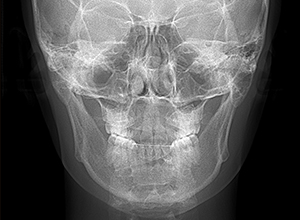

| X-Ray所見 | |

| セファロ所見 | 下顎枝、骨体部共に大きくしっかりとしており、バランスの良い形をしていた。上顎突出度は大きく、ANB6.0°と前後的にはⅡ級を呈していた。 |

| パノラマ所見 | 上顎両側第三大臼歯は存在して挺出が認められた。 |